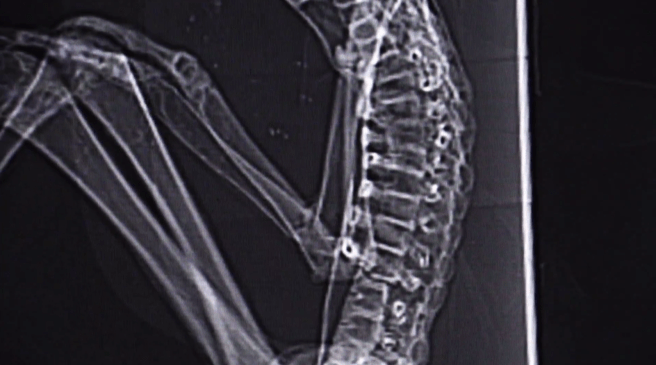

Pero cuando se mira a los rayos X, se puede ver que esa es la anatomía.

Esos huesos crecieron juntos.